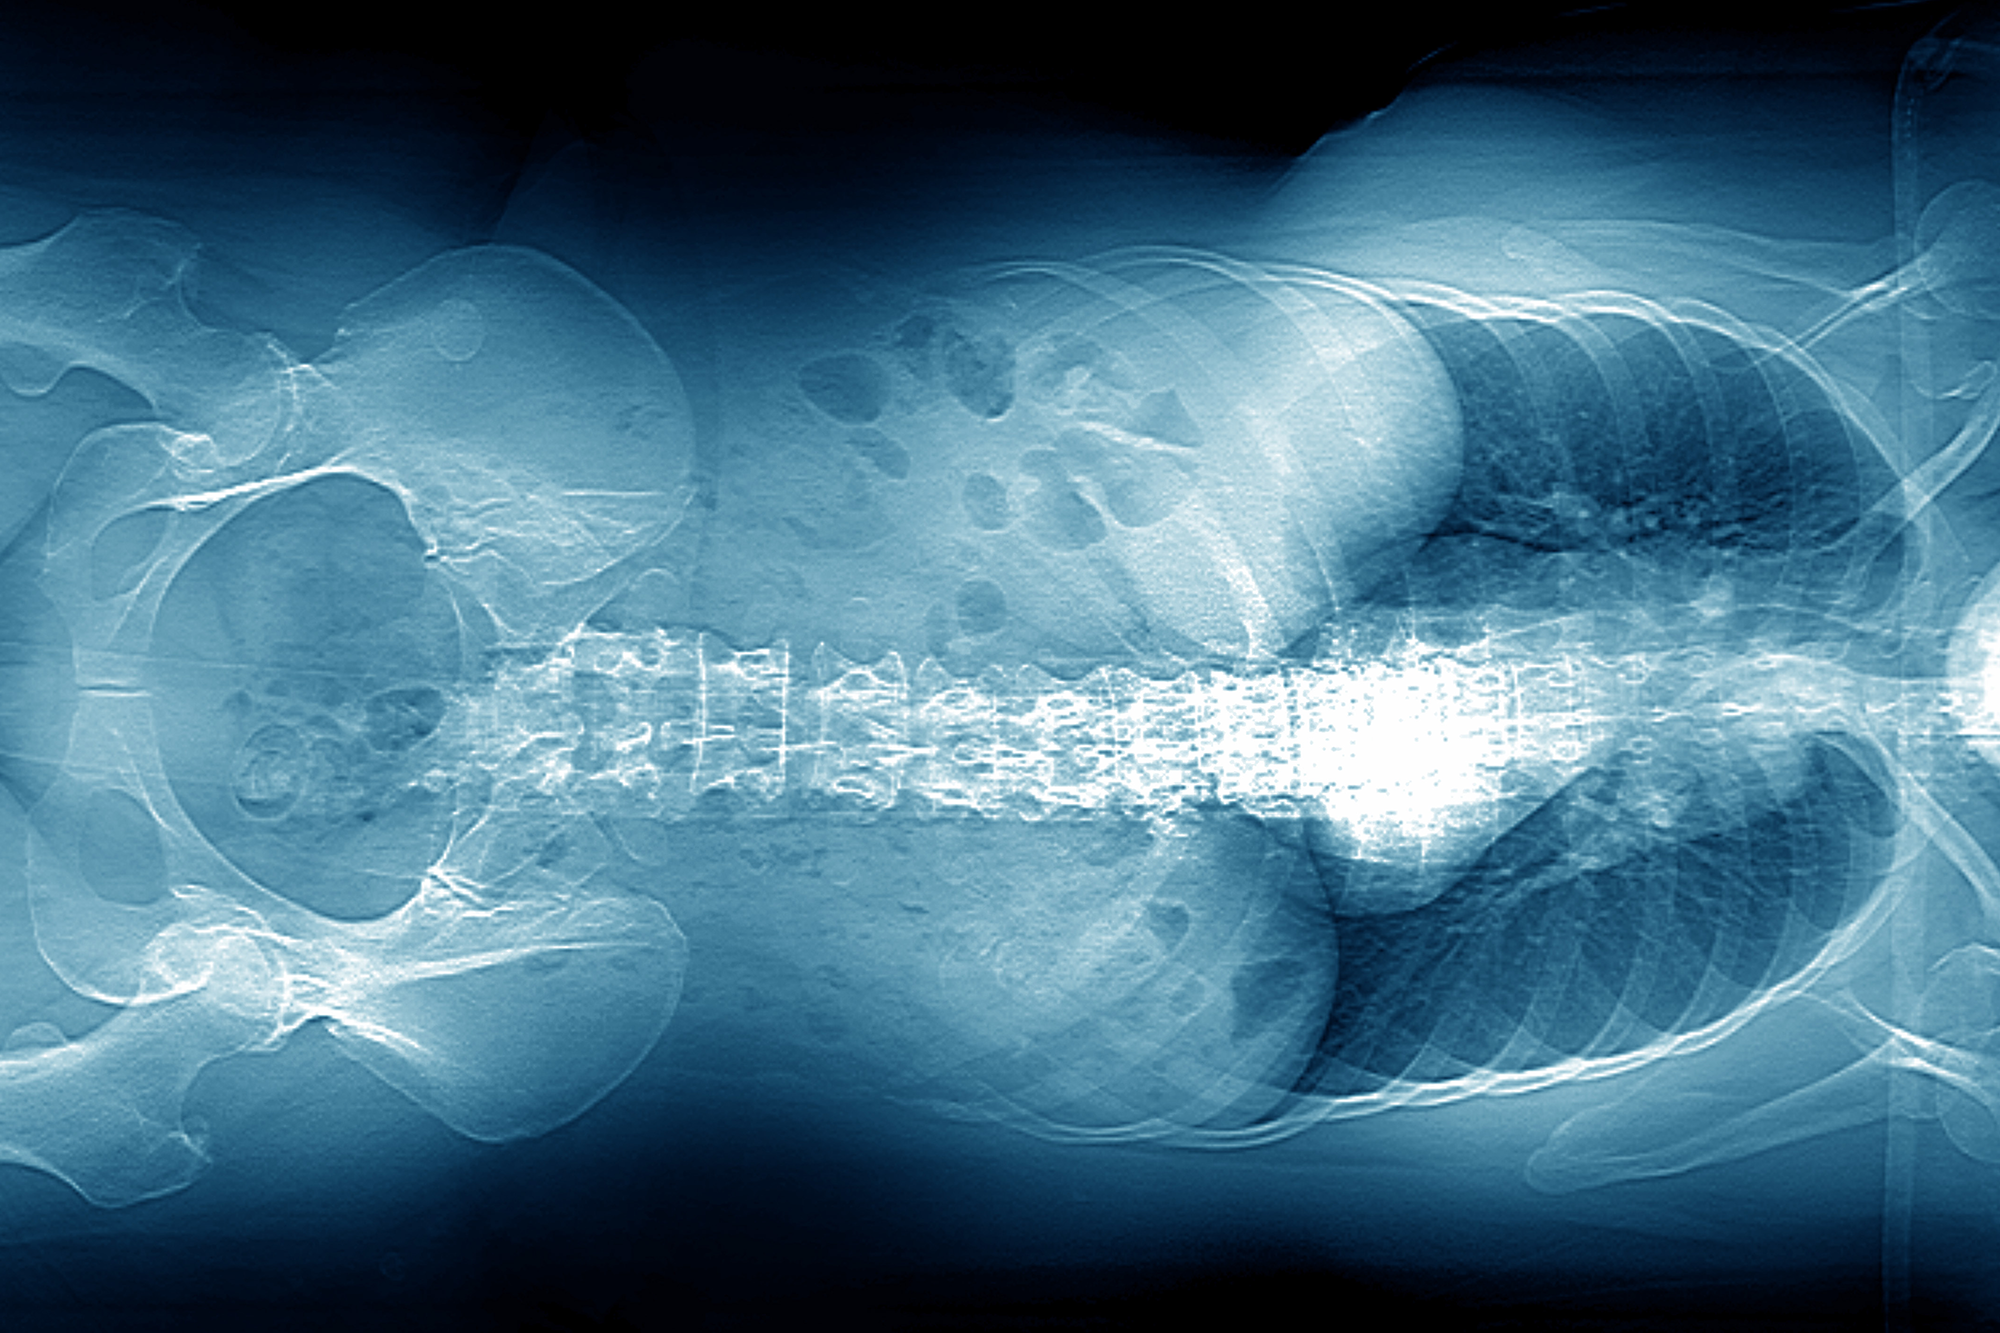

По утверждениям химиков, медицинским барием (0,05 (H2O)%) смертельно отравиться невозможно. При рентгеноскопии он обволакивает слизистую желудка и кишечника, позволяет врачам увидеть четкую картину, но при этом не всасывается и через желудочно-кишечный тракт полностью выводится из организма. А промышленный барий токсичен, всасывается организмом и нарушает работу внутренних органов.